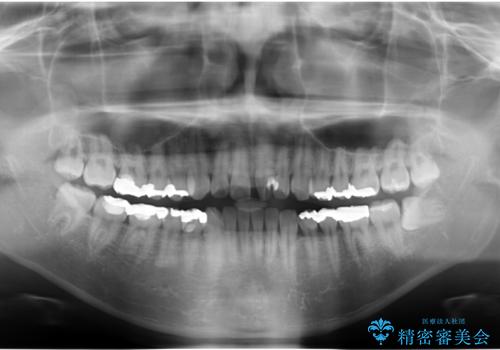

- 前歯のねじれを部分矯正で治療しました。

矯正前に、後戻り防止のため上唇小帯の処置を行っています。

奥歯のかみあわせも問題なく、また、下の前歯のがたつきが元からない場合は上の部分矯正が十分可能です。

上下親知らずの抜歯や虫歯処置も矯正前後で行っています。